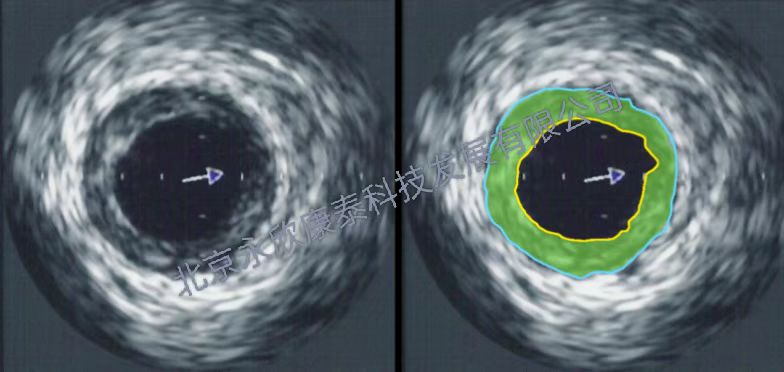

小型猪动脉粥样硬化模型一、高脂饲料喂养法造模机制: 在动物饲料中加入过量的胆固醇和脂肪。通常在一定范围内,饲料中胆固醇含量愈高,血浆中胆固醇含量升高亦愈明显,As病变发生也愈快。但血浆中胆固醇水平与As的形成和病变程度并非正相关,过高的血浆胆固醇水平常引起动物中毒甚至死亡。 二、造模方法: 小型猪:选用Gottigen系小型猪较为理想,用1%-2%高脂饲料饲喂6个月即可形成动脉粥样病变 三、相关检测评价: 1、血常规、血清血脂检测分析 2、超声评价斑块程度 3、CT、核磁成像 4、动脉取材、石蜡、冰冻病理切片 5、血管油红染色、马松masson染色 HE染色、免疫组化、荧光 6、肝脏油红染色 7、病理读片,分析斑块状态及面积比例 8、扫描电镜分析血管内皮病变 9、相关基因、蛋白分析。WB、QPCR